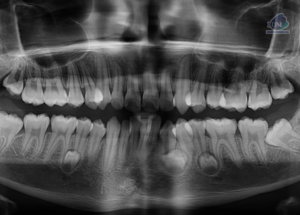

Caso 300 – IDM – HIPERPLASIA DE APÓFISIS CORONOIDES DE LADO DERECHO – IDM

Paciente femenino de 16 años acude al Instituto de Diagnóstico Maxilofacial (sede Miraflores) para evaluación quirúrgica. Radiografia Panorámica A la evaluación de la radiografía panorámica